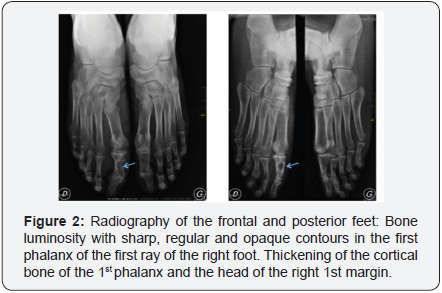

The mycological study concluded a fungal mycetoma by highlighting Aspergillus fumigatus in the tumor collection. The X-ray of the right foot performed in frontal incidence and 3/4 revealed bone luminosity with sharp, regular and opaque contours in the first phalanx of the first radius of the right foot. A thickening of the cortical bone of the 1st phalanx and the head of the right 1st margin was noted. There were no other abnormalities in the bones (Figure 2). CT scan of the feet without and with injection of contrast agent with reconstruction in soft parts and in bone window revealed bone deficits hypodense of cortico-medullary seat, interesting the diaphyso-epiphyseal regions of the first phalange of the right foot and the head of the 1st metatarsal. Their contours were sharp, regular and dense. The sesamoids were dense and atrophic. There was hypertrophy of the soft parts of the forefoot, enhanced after injection of contrast medium (Figure 3). No subcutaneous fluid collection was detected. These imaging aspects led to the conclusion that the 1st metatarsal head of the 1st metatarsal head and the 1st right foot phalanx with the thickening of the bone cortex and thickening of Soft parts of the tarsus facing.